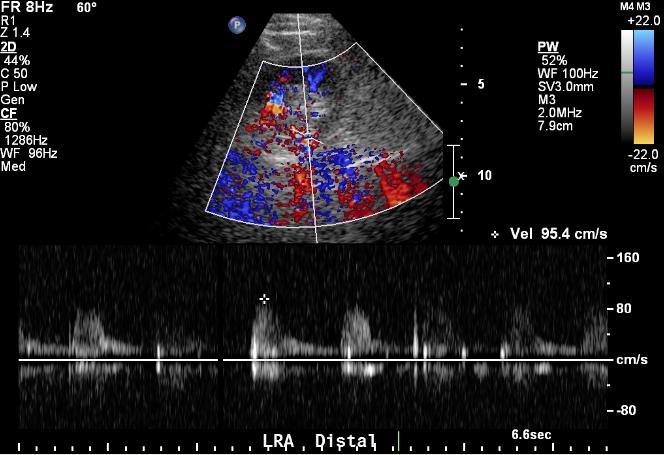

Distal renal artery ultrasound

There is partial visualization of the renal artery